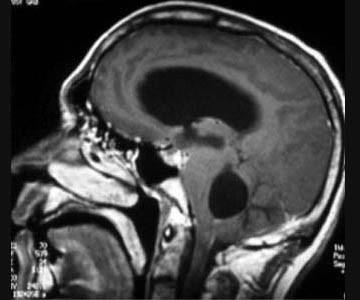

问题 根据MRI表现考虑何种真菌感染可能大 ( )

选项 A、念珠菌 B、以上均不是 C、新型隐球菌 D、曲霉菌 E、毛霉菌 一、单项选择题

答案 C